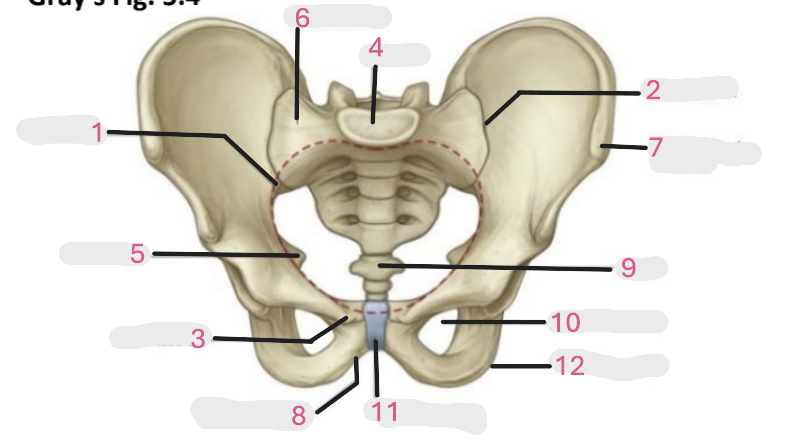

Where is the pelvic inlet

1

Where is the sacro-iliac joint

2

Where is the pubic tubercle

3

Where are the S1 body

4

Where is the ischial spine

5

Where is the ala of sacrum

6

Where is the anterior superior iliac spine

7

Where is the ischiopubic ramus

8

Where is the coccyx

9

Where is the obturator foramen

10

Where is the pubic symphysis

11

Where is the ischial tuberosity

12